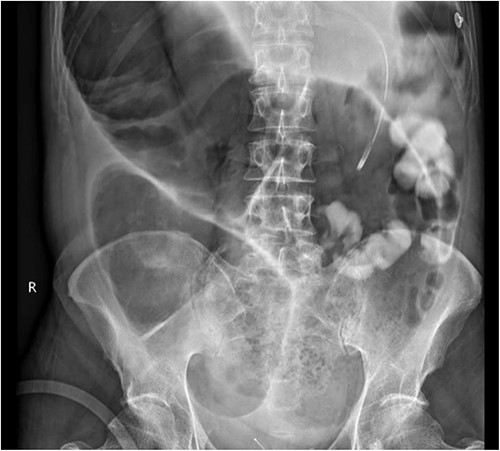

A week later, the patient reported new central abdominal pain with associated nausea and his last bowel action was almost 1 week prior. On examination, his abdomen was distended with generalized tenderness, but there was no peritonism. He was subsequently treated with regular oral laxatives, but with no improvement. A computed tomography (CT) abdomen and pelvis with oral and intravenous contrast was performed, which demonstrated marked faecal loading in the ascending and transverse colon with no convincing evidence of mechanical bowel obstruction (Fig. 1).

The colorectal team was consulted, and the patient received increased doses of aperients and suppositories as well as regular abdominal X-ray screening to monitor for colon dilatation. Despite this, the patient had minimal clinical improvement with ongoing abdominal bloating and pain and lack of bowel action, presenting a clinical dilemma of pseudo-obstruction, or AL with colonic involvement. A decision was made to proceed with flexible sigmoidoscopy, which found distended colon with faeces in the lumen, no mucosal changes to suggest ischaemia, and no obvious mechanical obstruction (Fig. 2).

A subsequent gastrograffin study was performed the next day with persistent contrast in nondilated small bowel at 8 hours and nil therapeutic clinical improvement (Fig. 3).

Gastrograffin study demonstrating markedly dilated gas filled loop of large bowel seen extending from the pelvis into the right upper quadrant, consistent with a dilated loop of redundant sigmoid, with no obvious contrast in the colon but some contrast in the small bowel loops in the left upper quadrant.